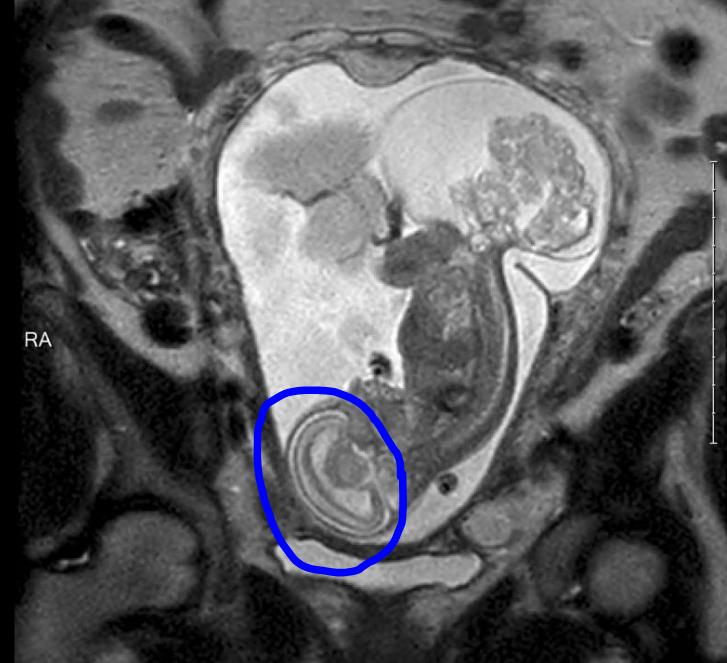

قام طبيب بإخراج طفلة من الرحم في الأسبوع 23 من الحمل ، وأجرى عملية جراحية عليه على عجل لإزالة الورم وإعادة الطفل إلى الرحم. في وقت لاحق ، ولدت الفتاة بصحة جيدة في الأسبوع 36 من الحمل.

الورم #المسخي_العجزي_العصعصي هو ورم يتطور قبل الولادة وينمو من العصعص عند الطفل ، وهو عظم الذنب.

كانت في الأسبوع 23 و 5 أيام من الحمل عندما أجرى كاس جراحة الجنين الطارئة. بحلول هذا الوقت ، كان الورم أكبر من الجنين تقريبًا.